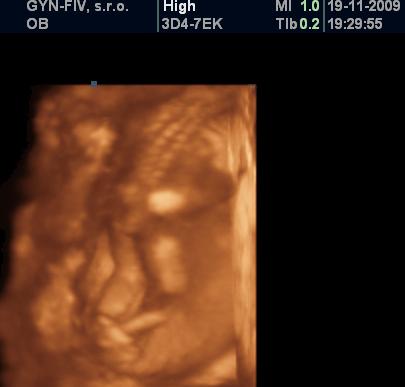

tesime sa na Jakubka🙂)